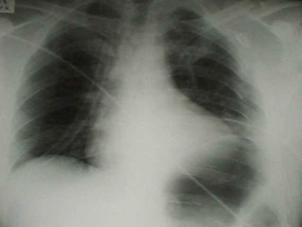

Contuzie pulmonara stanga Contuzie pulmonara dreapta

Contuzie pulmonara dreapta.Imagine CT